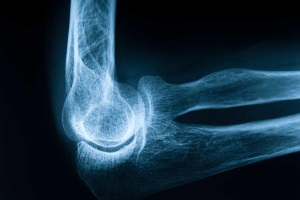

Остеопороз – распространенное и серьезное заболевание скелета, для которого характерно бессимптомное течение: очень часто при остеопорозе период мнимого благополучия внезапно завершается тяжелым переломом, способным стать причиной инвалидности.

Остеоартроз является распространенным заболеванием и составляет 10% в популяции во всем мире, а в Украине – 2,5%, что значительно ниже мировых показателей и связано с недостаточной выявляемостью данного заболевания.

Остеопороз – одно из основных заболеваний людей старшей возрастной группы, которое развивается при изменении метаболизма костной ткани в период старения организма и сопровождается уменьшением костной массы.

В Украине, как и во многих других странах, наблюдается увеличение числа лиц пожилого возраста. Старение организма сопряжено с остеоартрозом, спондилоартрозом, межпозвонковым остеохондрозом, спондилезом, остеопорозом и прочими заболеваниями.

Остеопороз – наиболее распространенное системное заболевание скелета, характеризующееся снижением костной массы и структурными изменениями костной ткани, которые выражены настолько, что даже при незначительной травме могут возникать переломы.